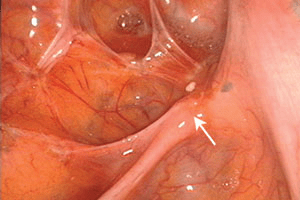

Figure 1. Les lésions symptomatiques d’endométriose du diaphragme (voir flèches) sont habituellement situées sur la partie postérieure de l’hémidiaphragme droit. Cette zone n’est pas facile à explorer à l’aide du laparoscope introduit par le nombril, mais est toujours visible lorsqu’on utilise un laparoscope de 5 mm avancé à travers la gaine musculaire située au-dessous du rebord costal droit, comme on peut le voir ici.

Figure 3 : Une endométriose discrète chez une adolescente peut être pratiquement incolore. Il est possible d’observer sur le ligament large gauche des papules claires et des macules blanchâtres, chacune avec une glande endométriosique (flèche) visible sous la surface péritonéale.

Figure 4 : Avec le temps, des lésions glandulaires incolores (flèches) peuvent secréter une substance paracrine pouvant déstabiliser les capillaires voisins et provoquer une hémorragie. Une légère fibrose du péritoine peut également survenir et masquer en partie les vaisseaux présents sous le péritoine. Une angiogenèse débutante est visible près du milieu de la zone hémorragique, conséquence de la sécrétion d’un facteur de croissance de l’épithélium vasculaire (VEGF).

Figure 5 : Avec le temps et en cas d’activité biologique suffisante, l’activité fibrotique et l’angiogenèse peuvent évoluer et cacher des foyers d’endométriose péritonéale. On peut toujours apercevoir d’autres structures glandulaires biologiques (flèches). Une petite agrafe utilisée lors d’une intervention chirurgicale précédente est visible dans le cul de sac de Douglas.

Figure 6 : La moitié supérieure de cette image montre le péritoine vésical, avec la partie antérieure de l’utérus au-dessous. Chez les patientes plus âgées, des lésions noires dites en « poudre brûlée » comme celles-ci sont plus proéminentes. Elles indiquent la présence de plus de lésions cicatricielles et de sang emprisonné sous la surface péritonéale.

Figure 7 : Chez cette patiente, les ovaires sont plus volumineux et accolés à la face postérieure de l’utérus. Le cul de sac de Douglas, caché en dessous, est complètement oblitéré. Beaucoup de chirurgiens interpréteraient cette image chirurgicale comme étant essentiellement une endométriose ovarienne associée à des adhérences, alors que l’interprétation correcte est celle d’une forme plus agressive d’endométriose du plancher pelvien et du rectum. Seule la dissection permet de trouver ces lésions additionnelles.